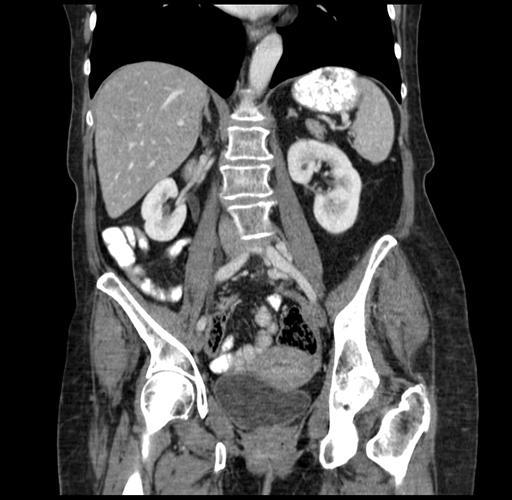

Axial Venous